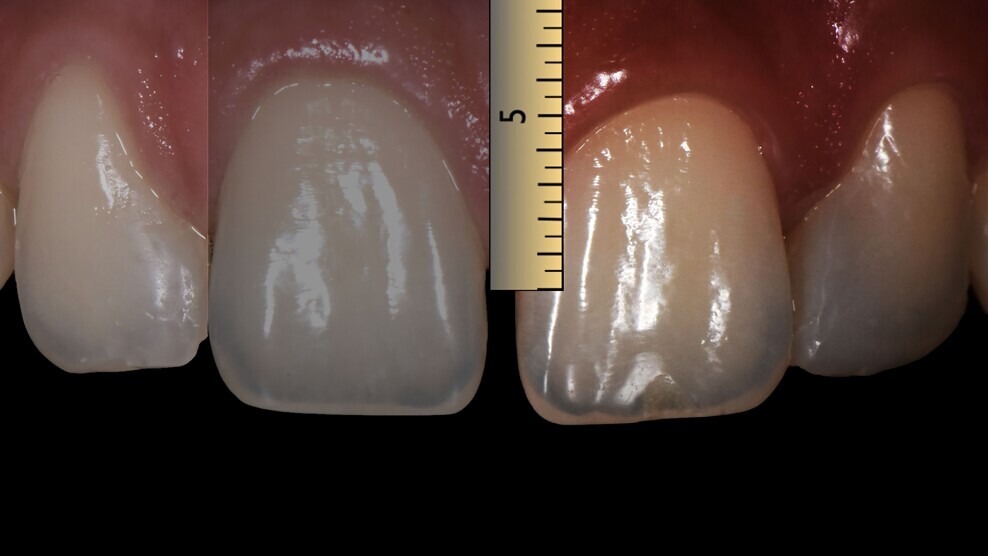

Fig. 3: Assessment of the distance between the contact point and the bone crest.

In order to avoid a negative gingival influence and an unaesthetic open gingival embrasure, the complete papillary filling of the interdental area was set as a goal. Among other concerns, black triangles are a plaque and food trap.2,3 For complete papillary filling of the interdental area, the distance between the proximal contact point and the crest of bone must be < 5 mm (Fig. 3).4